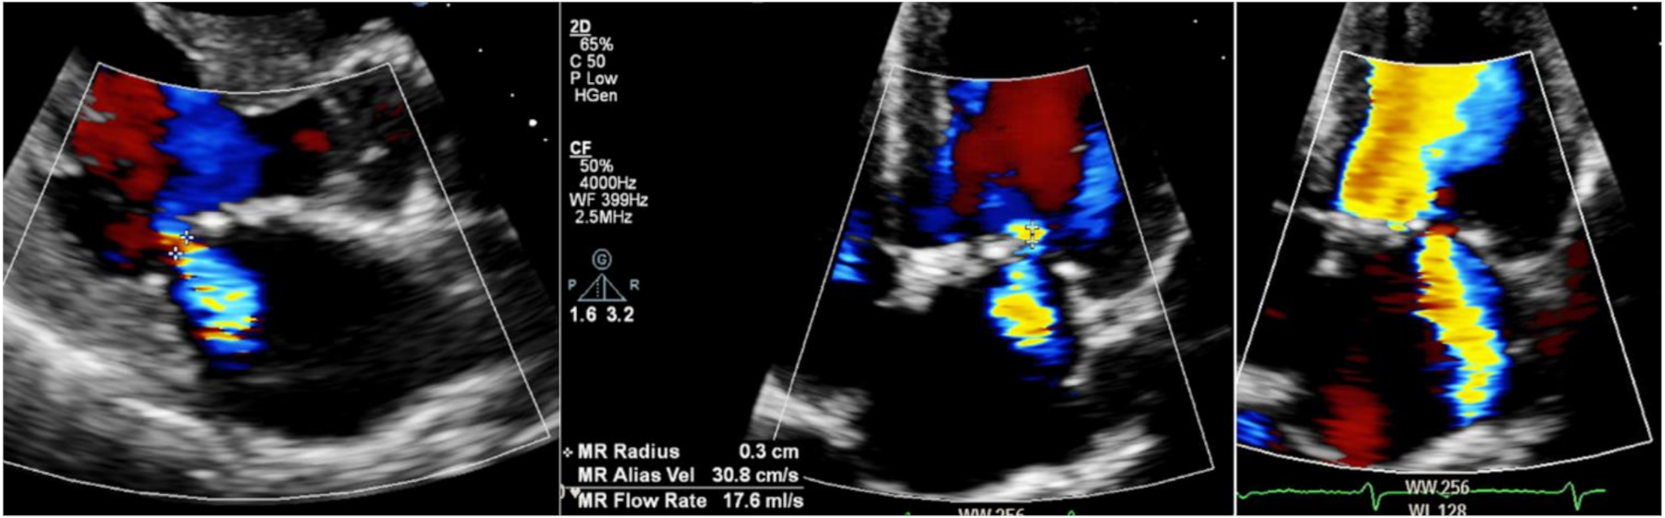

6.4. Valve Disease